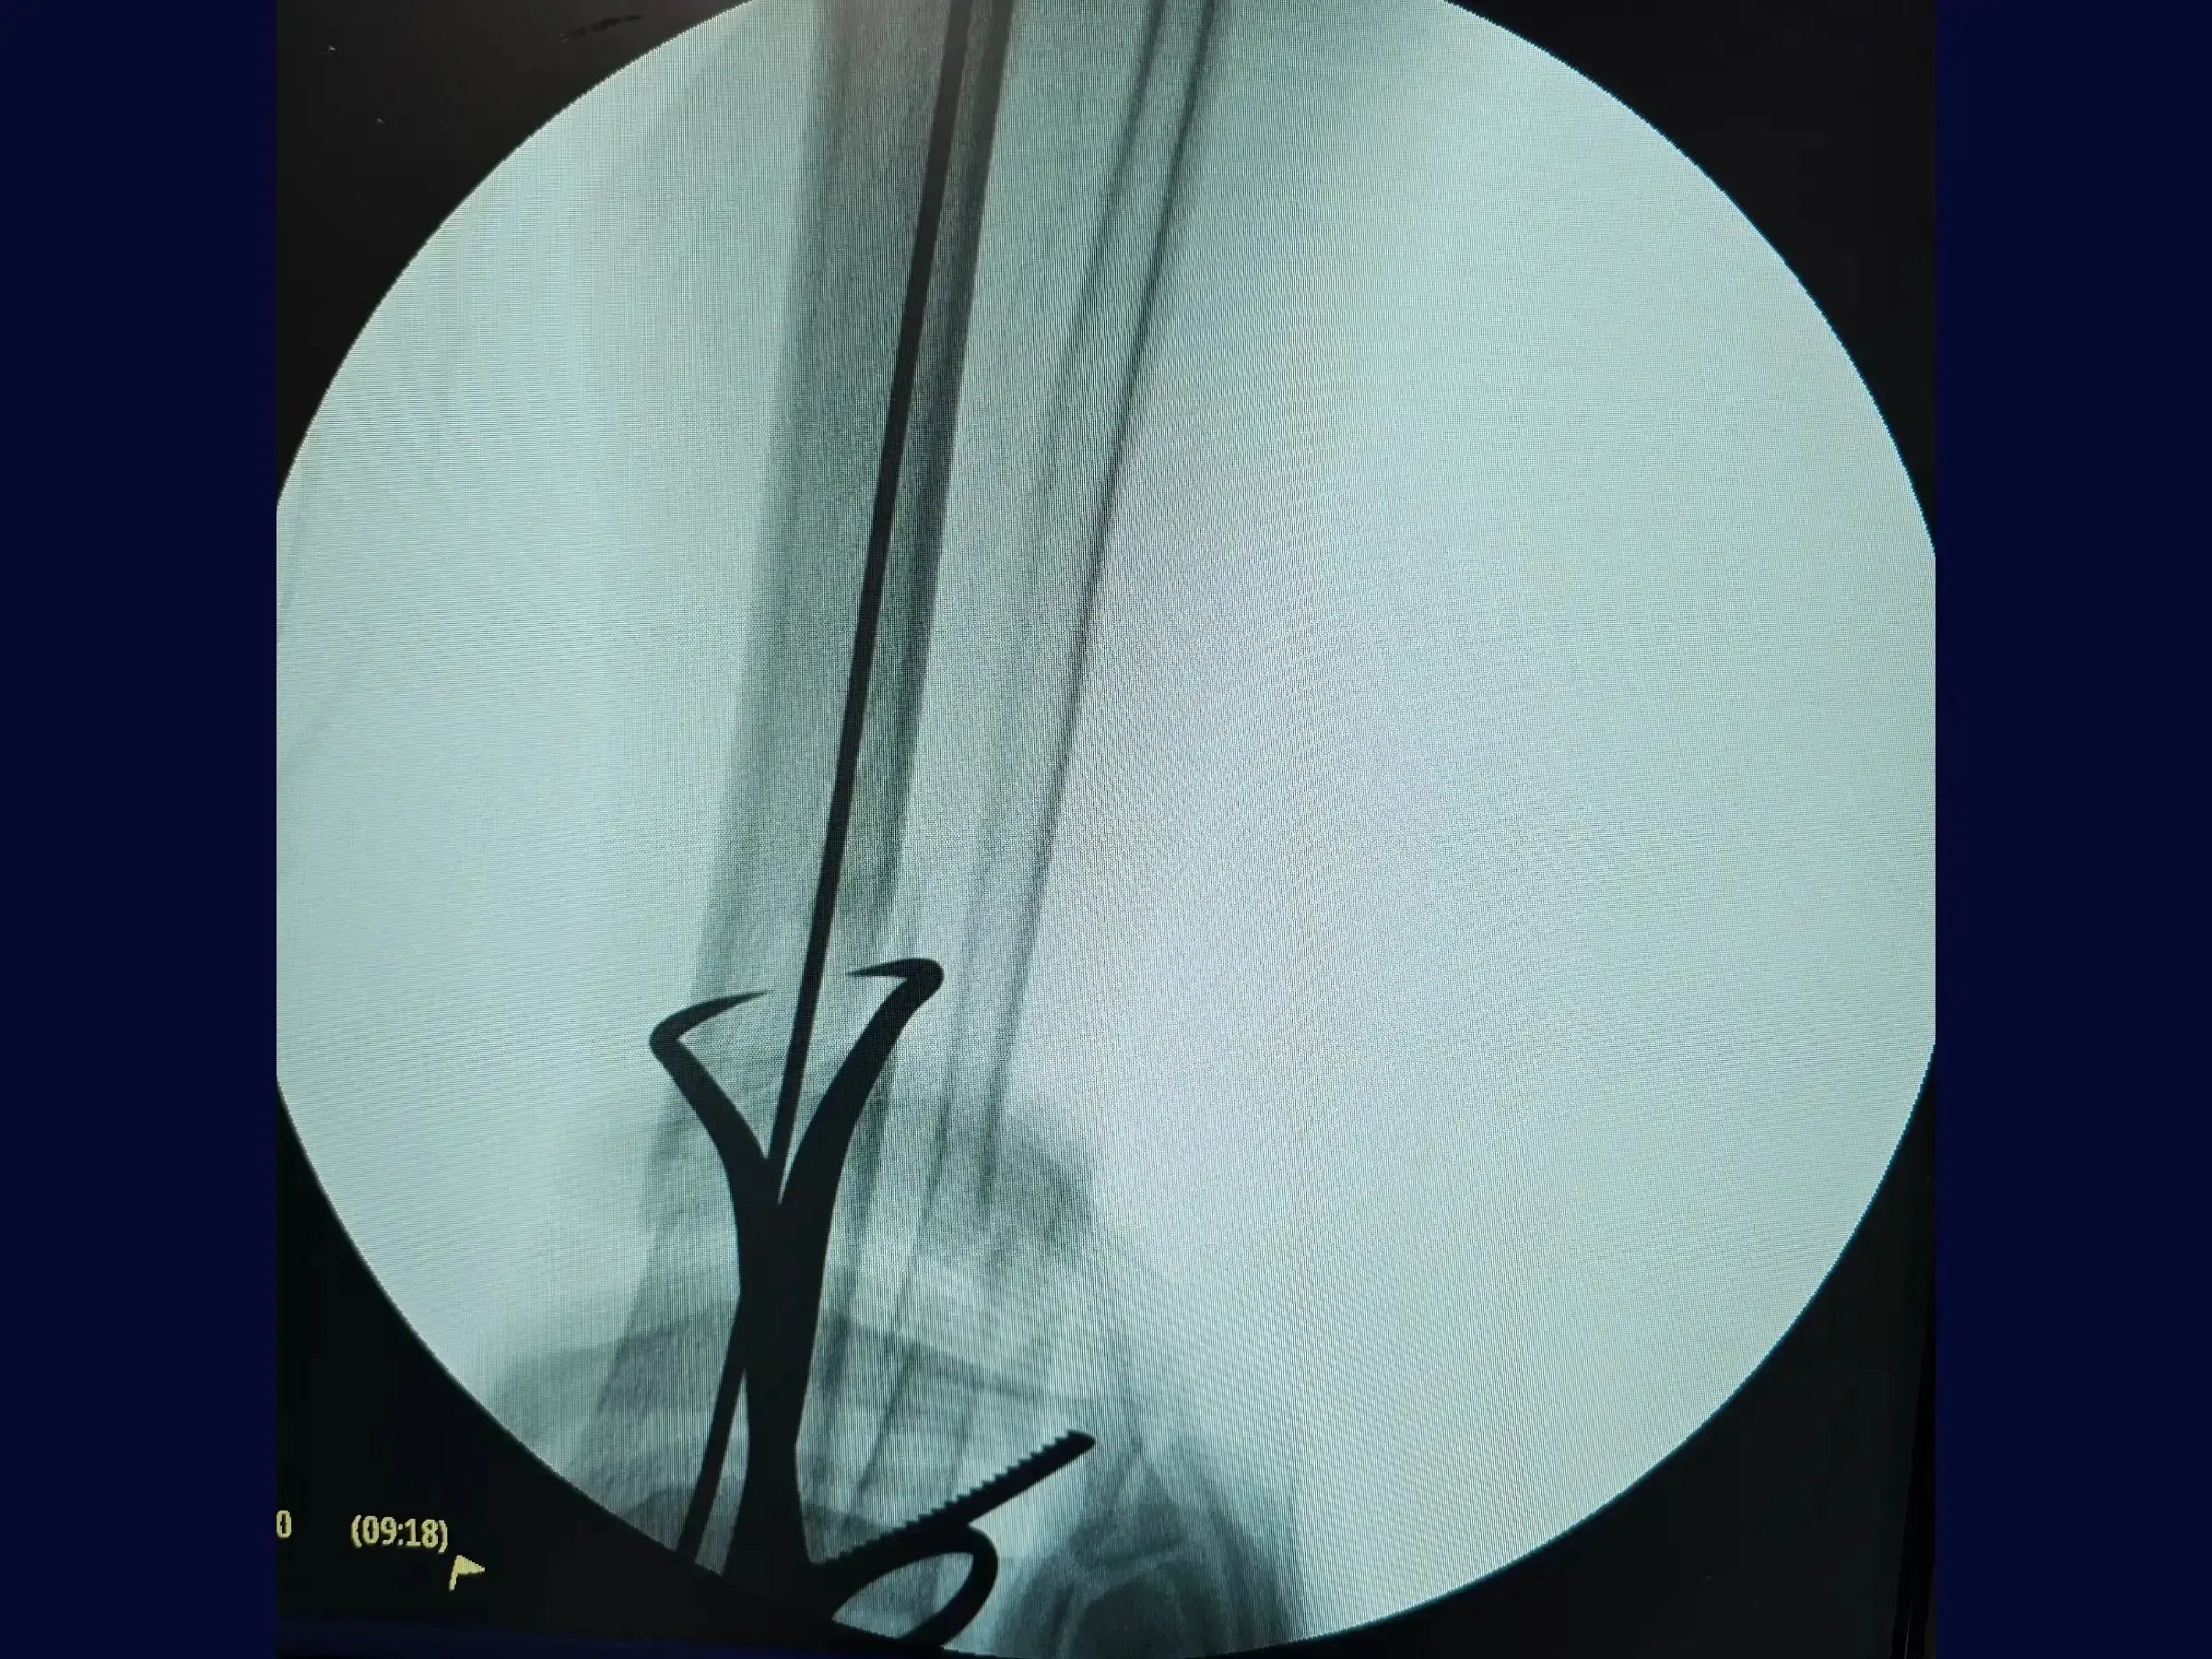

- Fresagem e Introdução da Haste Intramedular: Técnicas de fresagem para alargar o canal medular e introdução da haste de maior diâmetro, mantendo a camisa de proteção e protegendo a cartilagem articular.